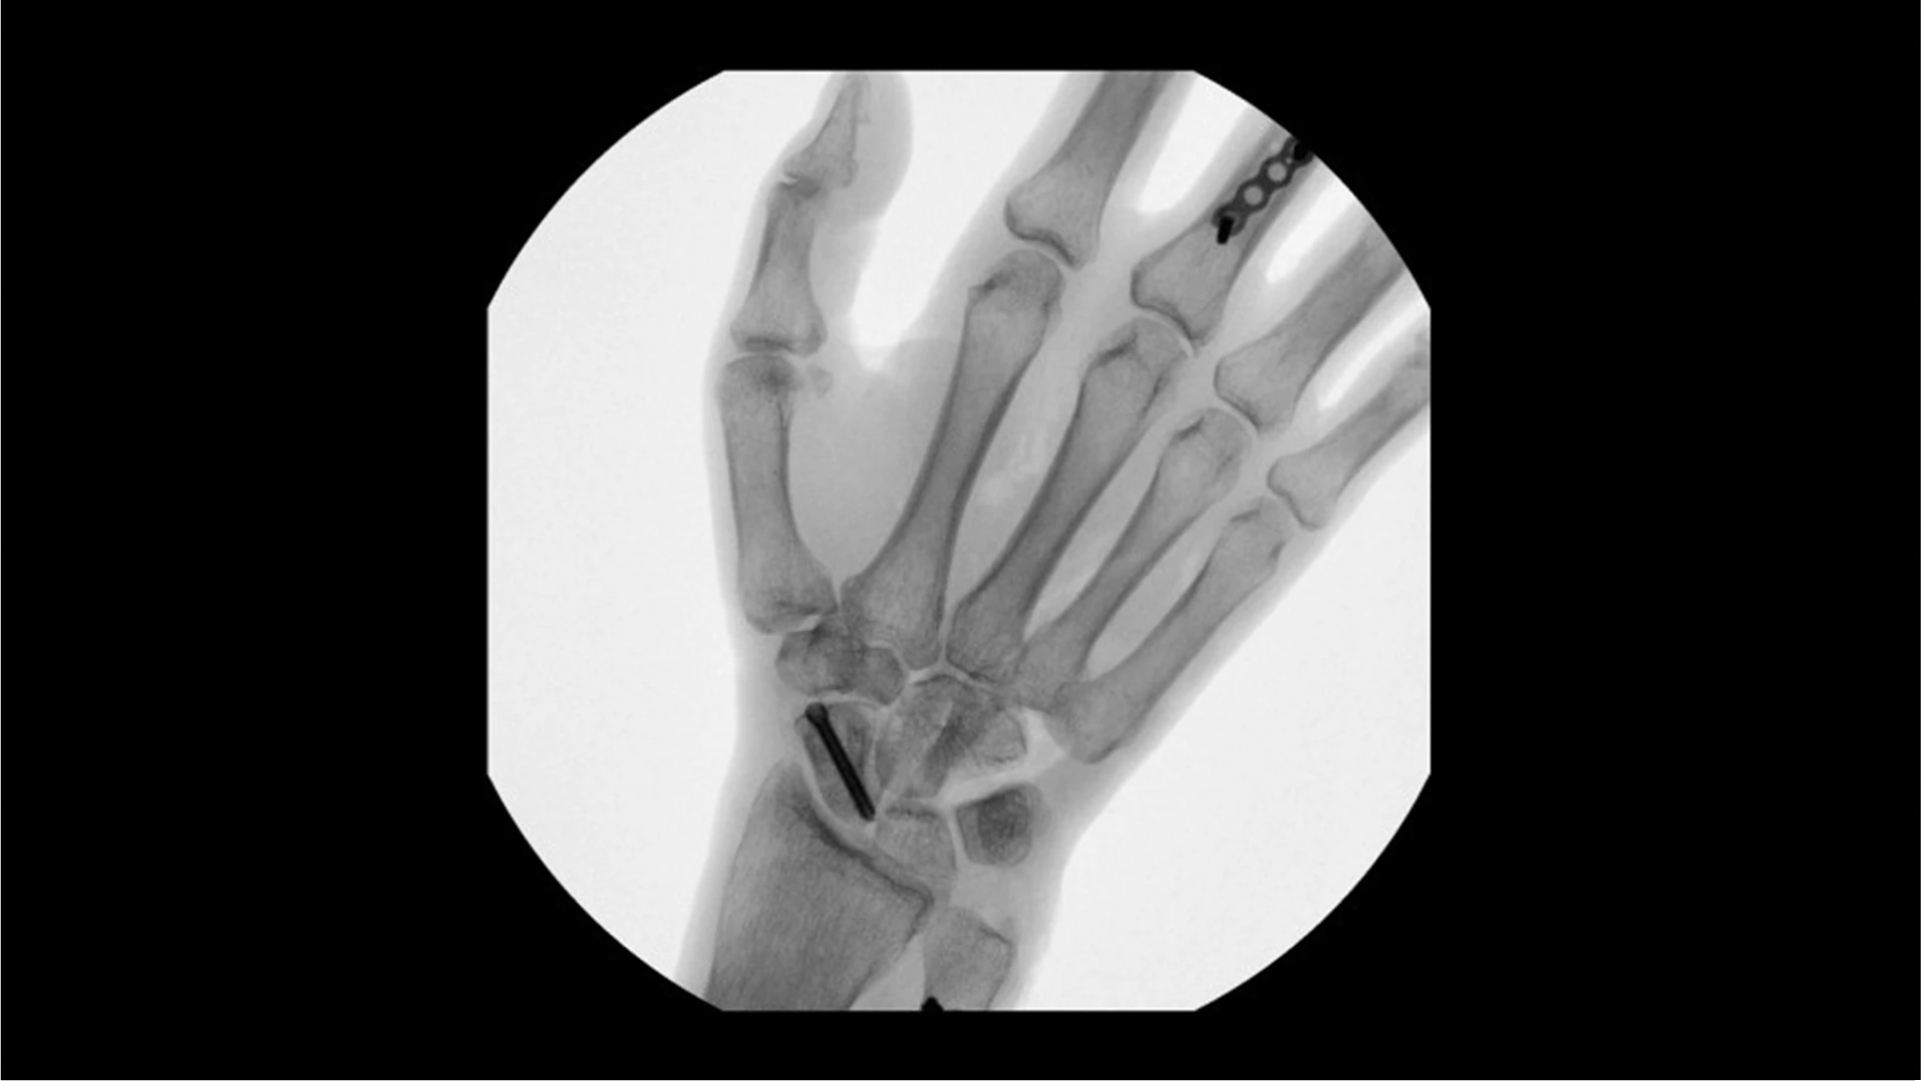

Visualizing small details such as bone fragments as well as assessing anatomical joint alignment is critical to increase clinical confidence during extremity imaging. With an OEC C-arm see clear, large images that enable you to accelerate clinical decisions and streamline your workflow during surgical procedures.

Increase clinical confidence by visualizing small details; such as bone fragments as well as assessing anatomical joint alignment with modern imaging tools such as Live Zoom, Digital Pen, and Fluorostore

Complex extremity procedures require powerful imaging systems. OEC premium C-arms perform imaging in a variety of procedures such as:

• Fracture reduction

• Scaphoid fixation

• Ulna fixation

• Distal radius fracture

• Metacarpal fixation